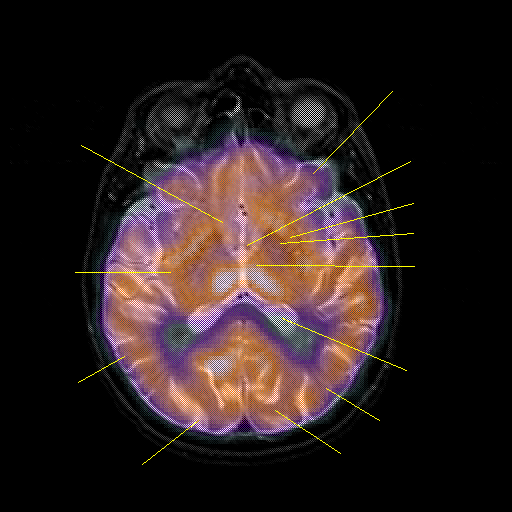

overlay : Slice 28

Slice 28

Pointers

Labeled